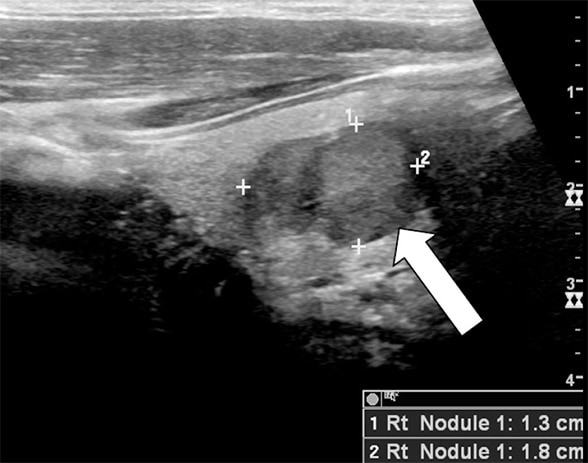

Thyroid ultrasound image showing a 1.8-cm nodule in right thyroid lobe (arrow), which proved to be medullary thyroid cancer.